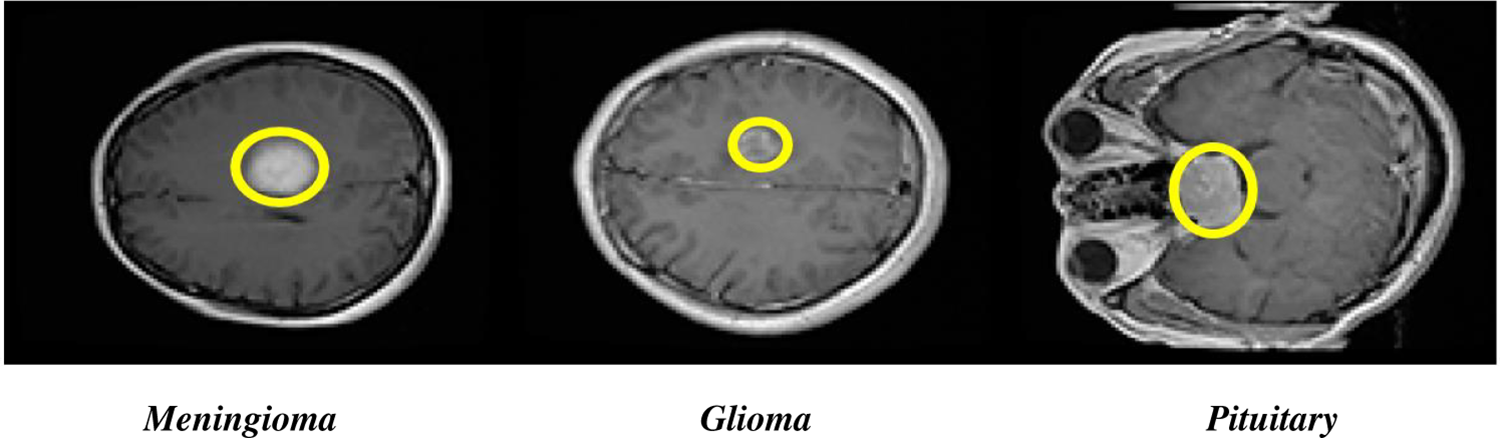

The human brain is like the control center for the human body. It takes information from our senses, processes it, and tells human muscles what to do. Abnormal growth of brain cells called brain tumors, can be a serious problem. Additionally, the World Health Organization (WHO) has categorized brain tumors (BTs) into four groups (Grades I–IV) based on how severe they are [1]. In the field of medical science, there has been a lot of development in several imaging techniques to aid in the diagnosis of diseases. These include X-rays, ultrasound, PET scans, CT scans, MRS, SPECT scans, and MRI [2]. These imaging technologies provide valuable insights for doctors to examine different parts of the human body, ensuring the diagnosis and treatment of various diseases. Among these, MRI stands out as the preferred and most valuable method because it shows images with high resolution and provides accurate details about the structure of the body. It is especially effective in capturing many types of brain tumors like Glioma, Pituitary tumors, and Meningioma [3]. Fig. 1 shows the brain tumor types. In fact, MRI is widely regarded as one of the most reliable and widely used tools for classifying brain tumors. Grade III and Grade IV BTs are especially fast-growing tumors and can spread to other parts of the body, harming different healthy cells. Detecting and identifying BTs early is crucial because it helps doctors to plan the right treatment, using tools like MRI and other images [4].

Figure 1: Axial view of Glioma, Pituitary brain tumors, and Meningioma types

There are three types of primary brain tumors: Glioma, Pituitary tumors, and Meningioma. Pituitary tumors are generally non-cancerous that grow in pituitary glands, which produce vital hormones in the body [5]. Gliomas develop from specific brain cells called glial cells [6]. Meningioma tumors usually grow on the protective and outer membrane that covers the spinal cord and brain [7]. Identifying the difference between normal brain tissue and abnormal tissue is vital when looking for BTs. Due to differences in size, shape, and location, detecting BTs can be challenging and still an ongoing problem to be addressed. The field of medical images processing plays an important role for BT analysis, including tasks like classification, segmentation, and detection [8,9]. The accurate classification of brain tumor is necessary to diagnose the tumor type timely if it exists. Modern diagnosis systems aided by computer in biomedical image processing to help radiologists in guiding patients and improve BT classification [10,11]. For brain tumor categorization, the use of advanced and pre-trained CNN models has made great progress, allowing researchers to make speedy and accurate decisions. Due to the complexity of data, categorizing brain images with high accuracy remains a difficult challenge. Using publicly available datasets, this study aims to develop a completely automatic CNN model that performs color transformation and selects optimized features for identifying brain tumors into different categories.